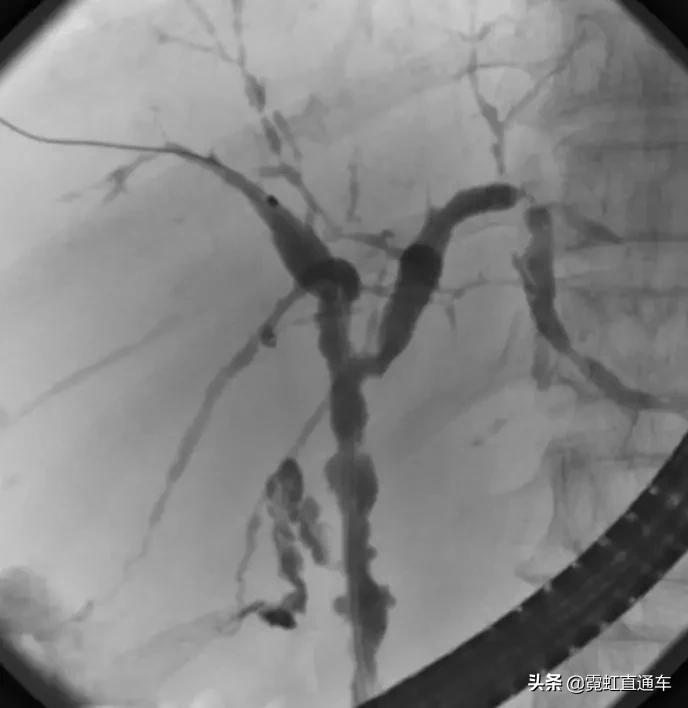

A.胆道影像学检查

1)特异性胆管征象

2)非特异性胆管征象

ERCP:胆管狭窄与扩张交互,呈串珠状改变

多发短小狭窄,胆管环状受累

PTCD:胆管呈边缘不整羽毛状

ERC:胆管壁呈憩室样突出